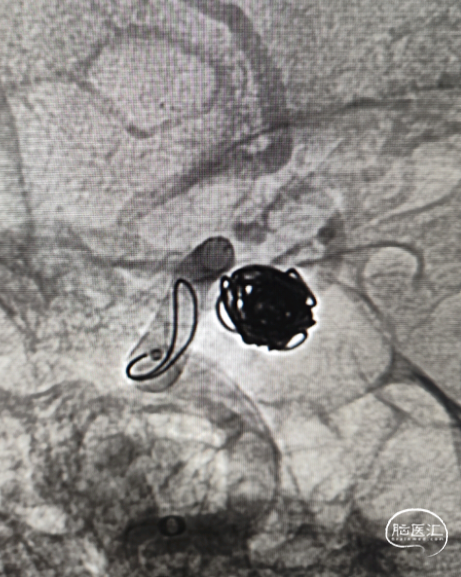

全身麻醉,6F 长鞘+6F 115cm Tethys®中间导引导管建立通路。动脉瘤为窄颈,填圈顺利,填入Jasper®弹簧圈 7mm*30cm、5mm*10cm、4mm*10cm三枚。

眼动脉弯近端直径最大到5.0mm,远近端差别大,支架尾端尽量不落在5.0mm的区域,所以选择支架 4.5*16。右侧大脑中动脉打开后,回撤定位。

支架释放。

术后造影。